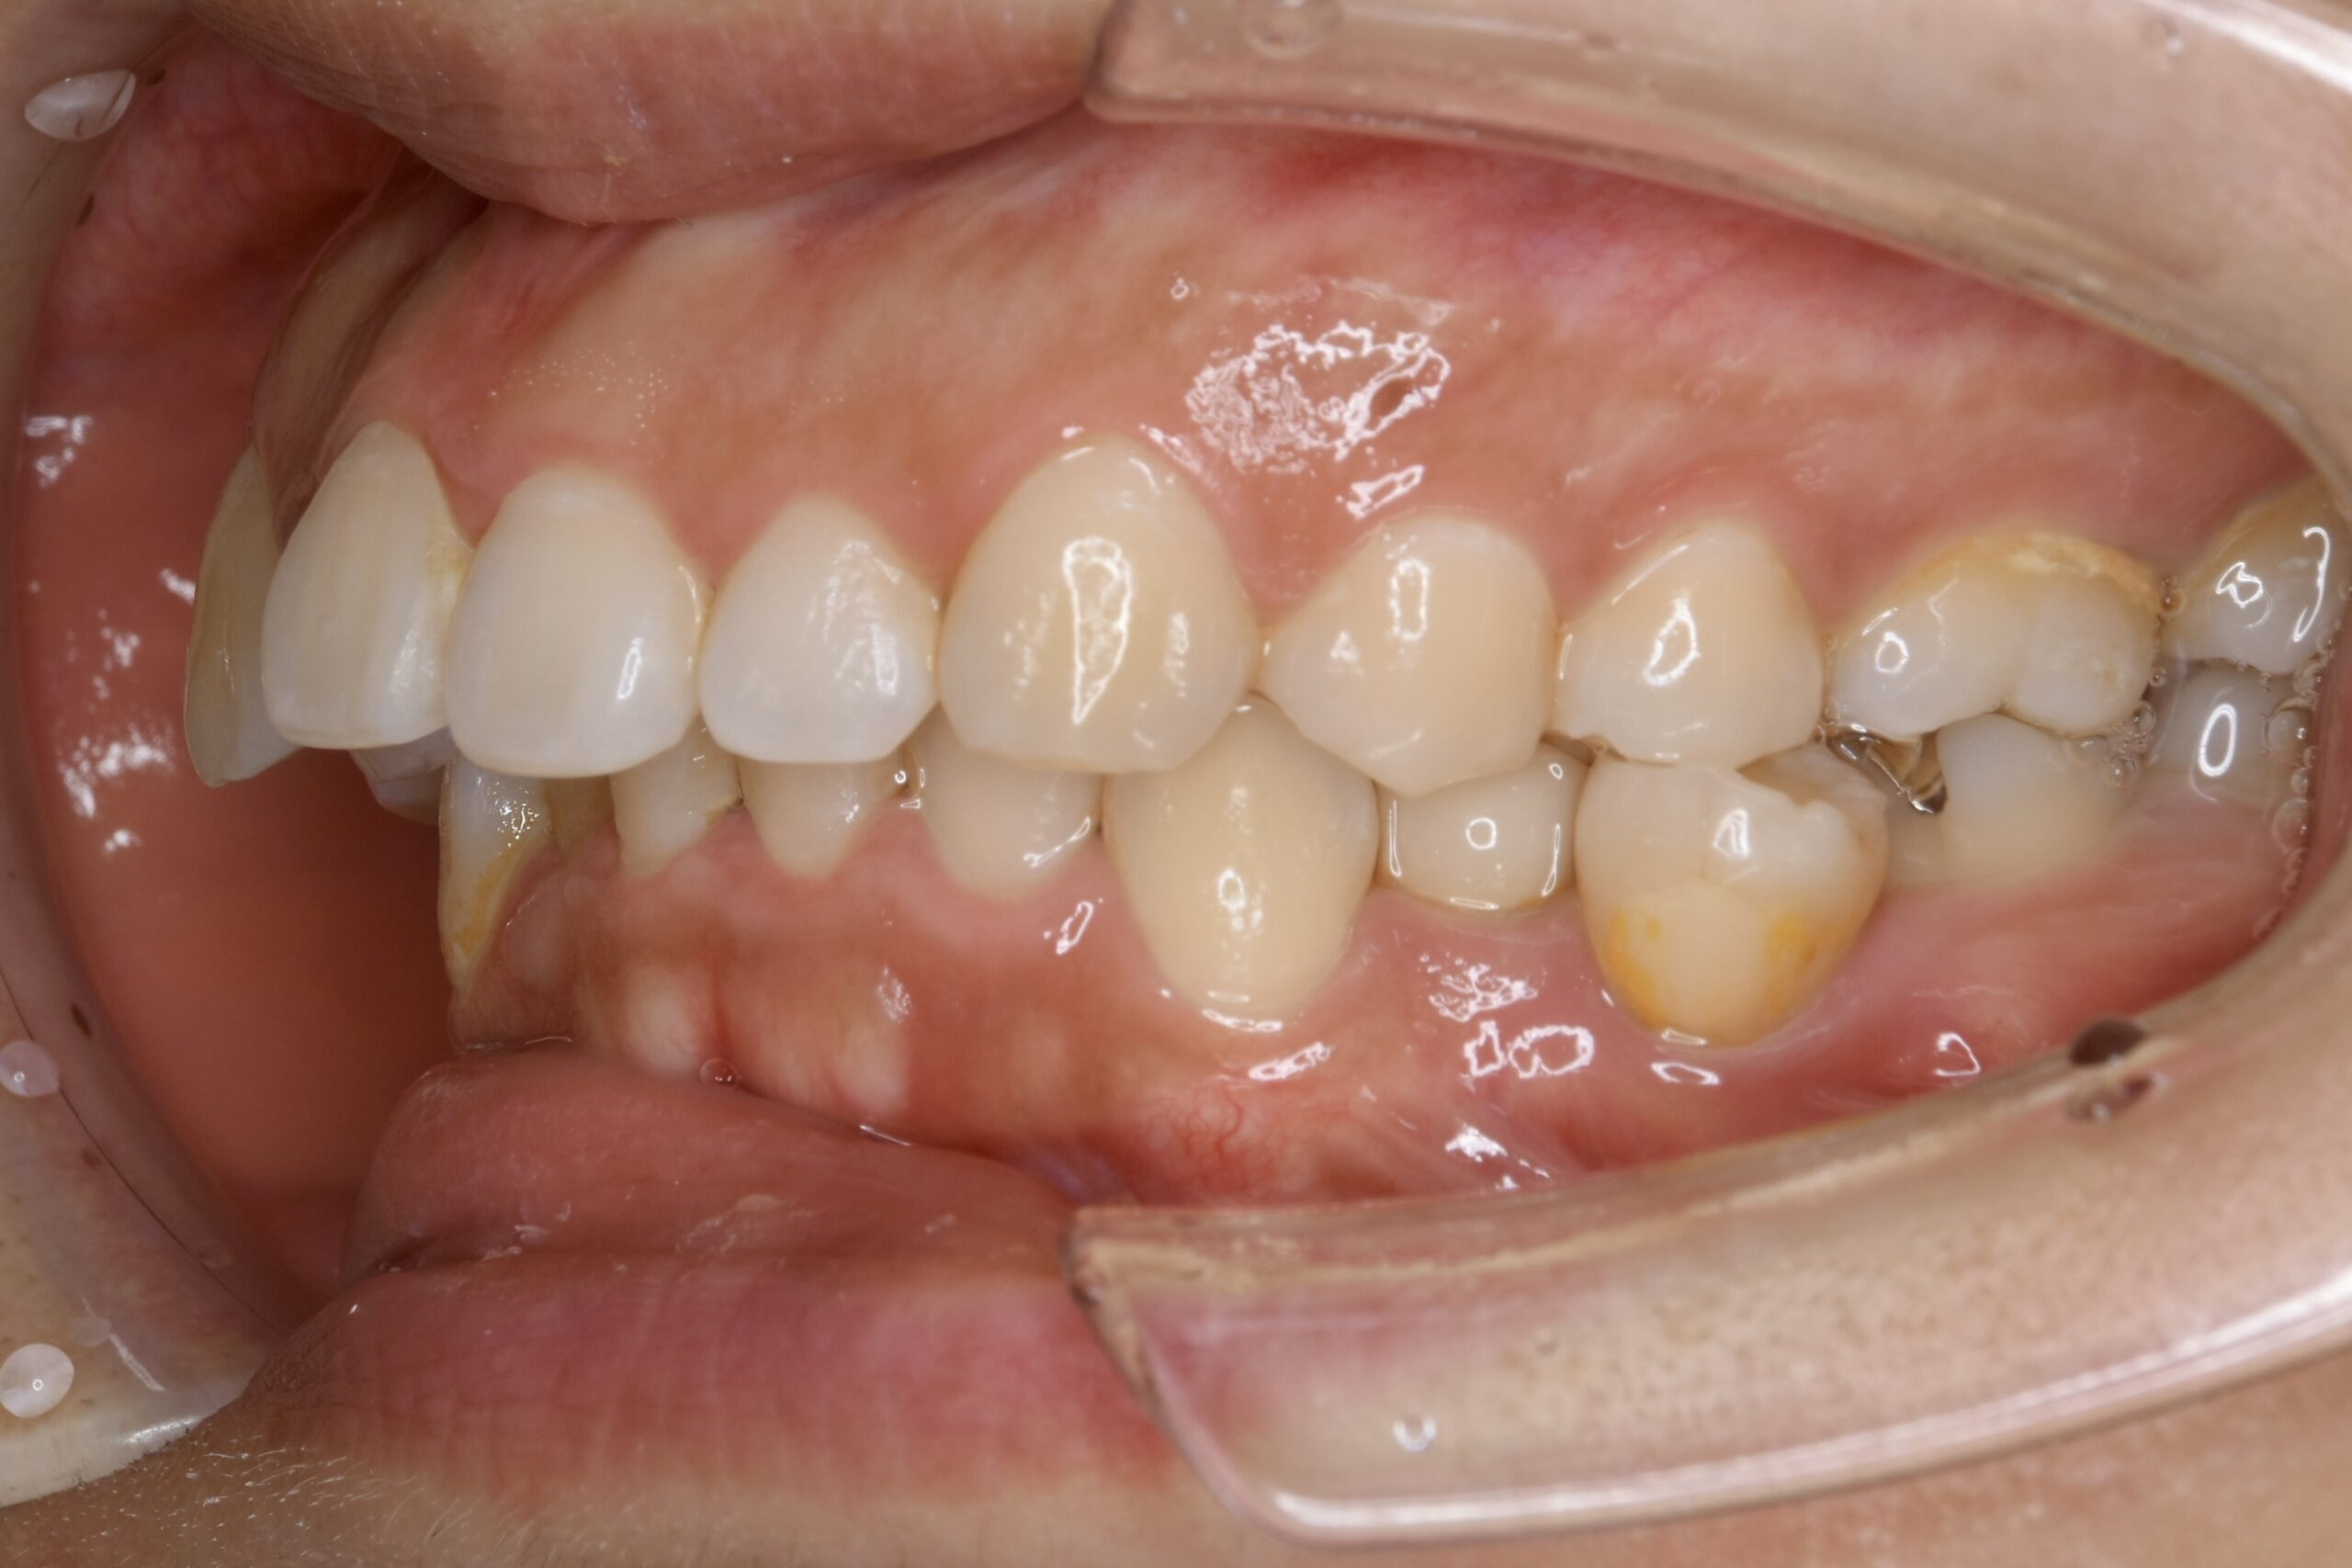

32歳 女性 治療期間:1年7ヶ月

AFTER

診断名・主な症状 叢生を伴う上顎前突

治療内容 上下とも歯を2本抜いて、上の前歯を後方に引きながら、でこぼこを治しました。

使用装置 マウスピース矯正装置(インビザライン)

抜歯部位 上 両側4番目

下 右側4番目、左側5番目